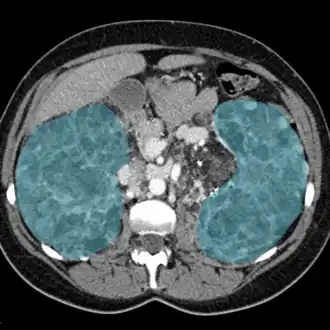

| Rins inflamados em exame de ressonância magnética (em azul). | |